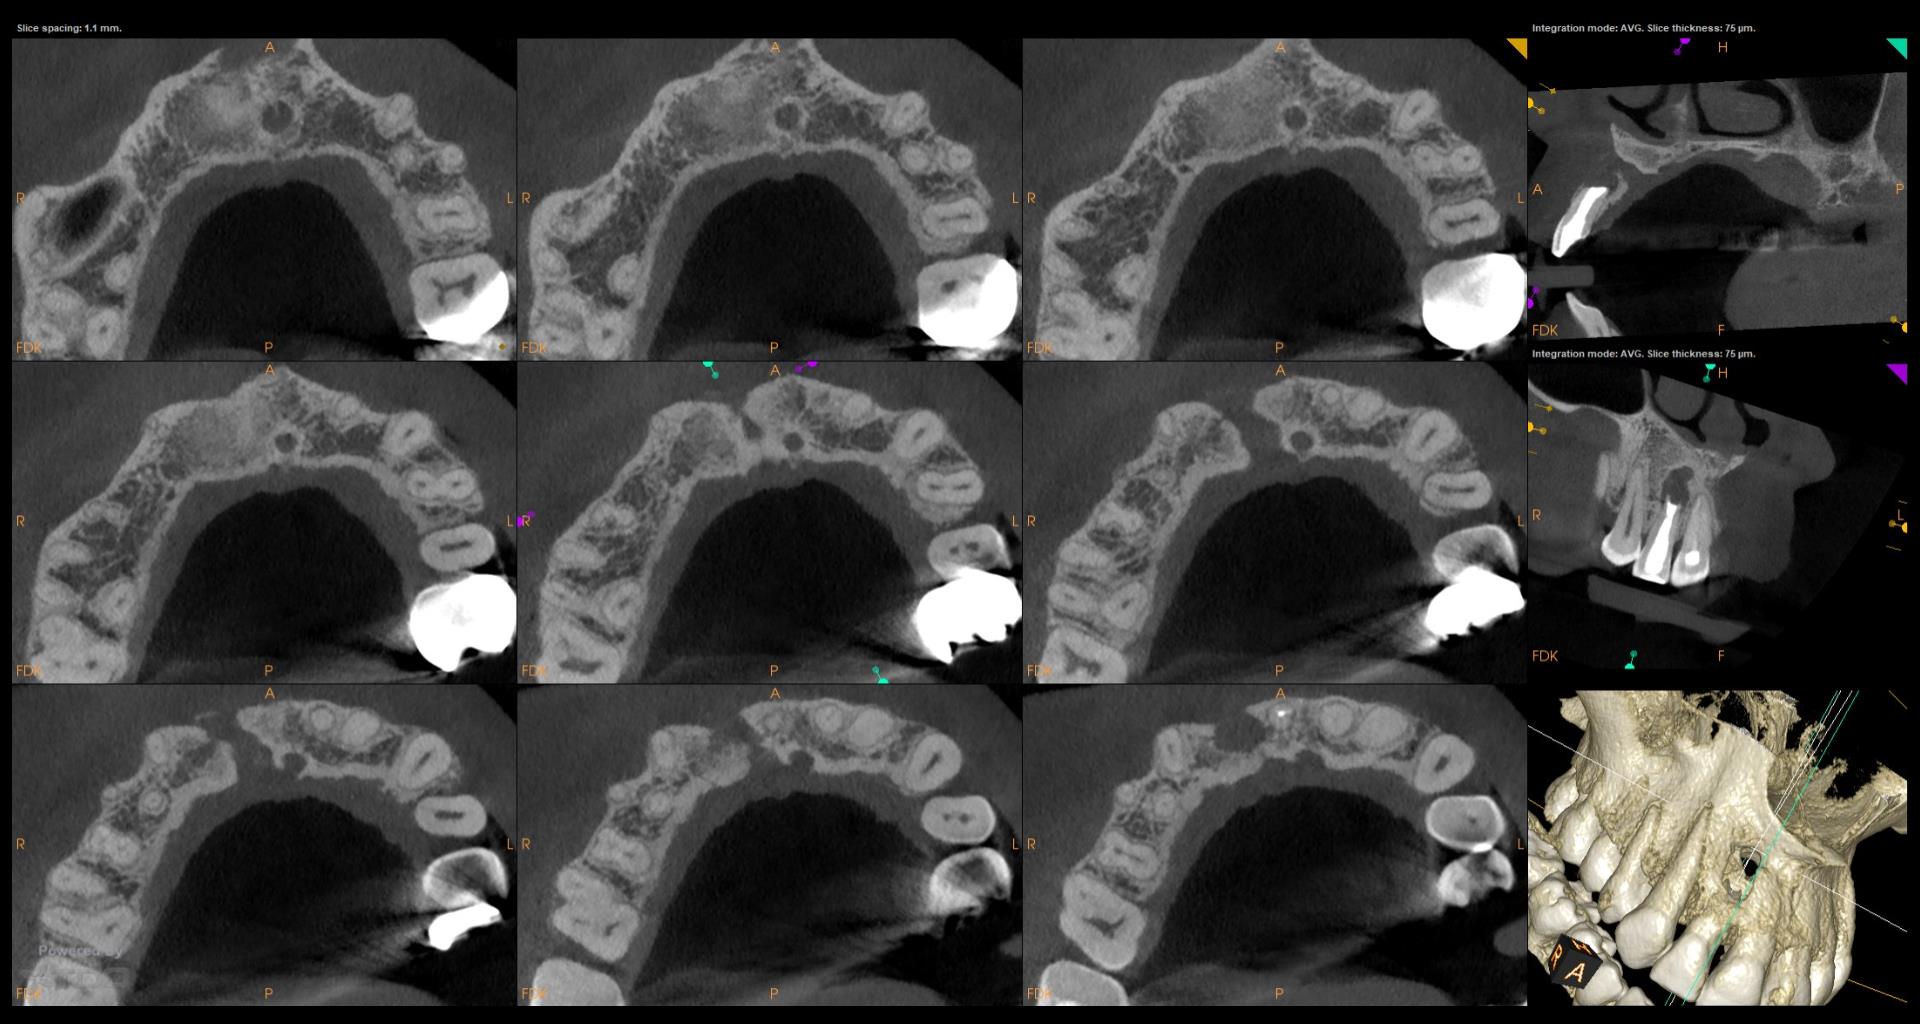

Do you have the previous review x ray s,